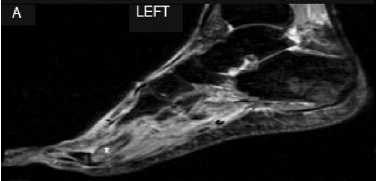

Finally, the condition of immunosuppression-related bone marrow edema syndrome came up (also known as posttransplant bone marrow edema syndrome and calcineurin inhibitor pain syndrome). This syndrome typically presents with symmetrical pain in knees or feet associated with mildly elevated alkaline phosphatase and normal ESR/CRP. The pathophysiology is not clearly understood but it seems to be related to intra-osseous vasoconstriction. CNIs have been raised as possible culprits. A MRI imaging can usually confirm the diagnosis, showing bone marrow and periarticular soft-tissue edema and absence of avascular necrosis. Despite the possibility of severe symptoms, this condition usually regresses spontaneously, being most prevalent on the first three months after transplant. Our patient was transitioned to sirolimus without improvement. After reduction of immunossuppression, her symptoms gradually improved in the following 3 months, with associated resolution of edema on MRI.

Figure: MRI showing bone marrow edema.